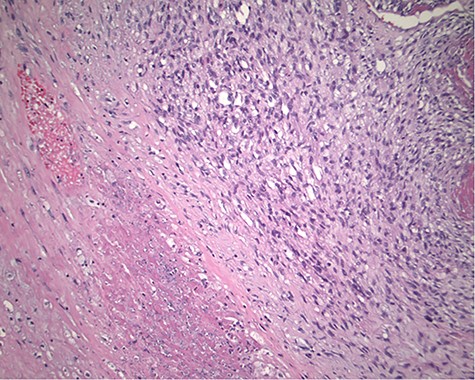

The pathology revealed a 282-g nodular tumor measuring 10.7 × 8.5 × 7 cm that was grossly tan, fibrotic and firm with focal yellow discoloration and soft flesh areas (Fig. 6). Microscopic analysis revealed high-grade spindle cell sarcoma arranged in intersecting fascicles with extensive areas of necrosis (Fig. 7). The lesional cells had fibrillary eosinophilic cytoplasm and evoid nuclei with nuclear pleomorphism (Fig. 8). Areas of rhabdomyoblastic and chondroid differentiation were also noted (Figs 9 and 10). Immunostaining was positive for desmin, focally for CD 34 and Bcl2, while Cam 5.2, CD117, S-100, SMA and HME45 immunostains show patchy staining for myogenin. Expression of H3K27me3 was completely lost in the tumor cells. MyoD1, SOX10, MDM2 and CDK4 were negative. It was identified as a high-grade MPNST with heterologous rhabdomyosarcomatous differentiation, i.e. MTT. All margins were negative.

Magnification 200× Spindle cells with mild to moderate nuclear pleomorphism and focal rhabdomyoblastic differentiation.